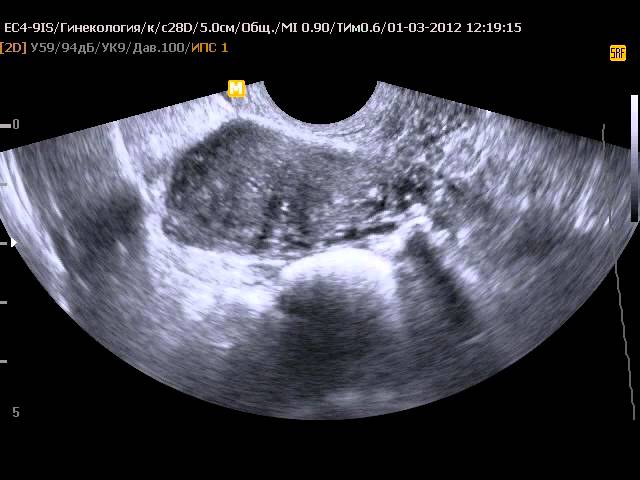

Диагностировать данное состояние достаточно легко. Оно хорошо визуализируется при ультразвуковом исследовании, при этом точность диагностики более 90%, то есть вероятность ошибки почти полностью исключена. Кроме того, заподозрить наличие такой патологии можно и при бимануальной (ручной) пальпации нижней части брюшной стенки.

| Диагностика | УЗИ, гистеросальпингография, лапароскопия. | Стандартные гинекологические осмотры, УЗИ. |

Редкость и диагностика: Рудиментарный рог матки встречается довольно редко, и его диагностика может быть сложной. Часто аномалия выявляется случайно во время ультразвукового исследования или других визуализирующих методов, таких как МРТ, особенно если у женщины нет явных симптомов.

Диагностика обычно включает ультразвуковое исследование, которое позволяет визуализировать анатомические особенности матки. В некоторых случаях может потребоваться магнитно-резонансная томография (МРТ) для более детального изучения структуры матки и выявления возможных аномалий.